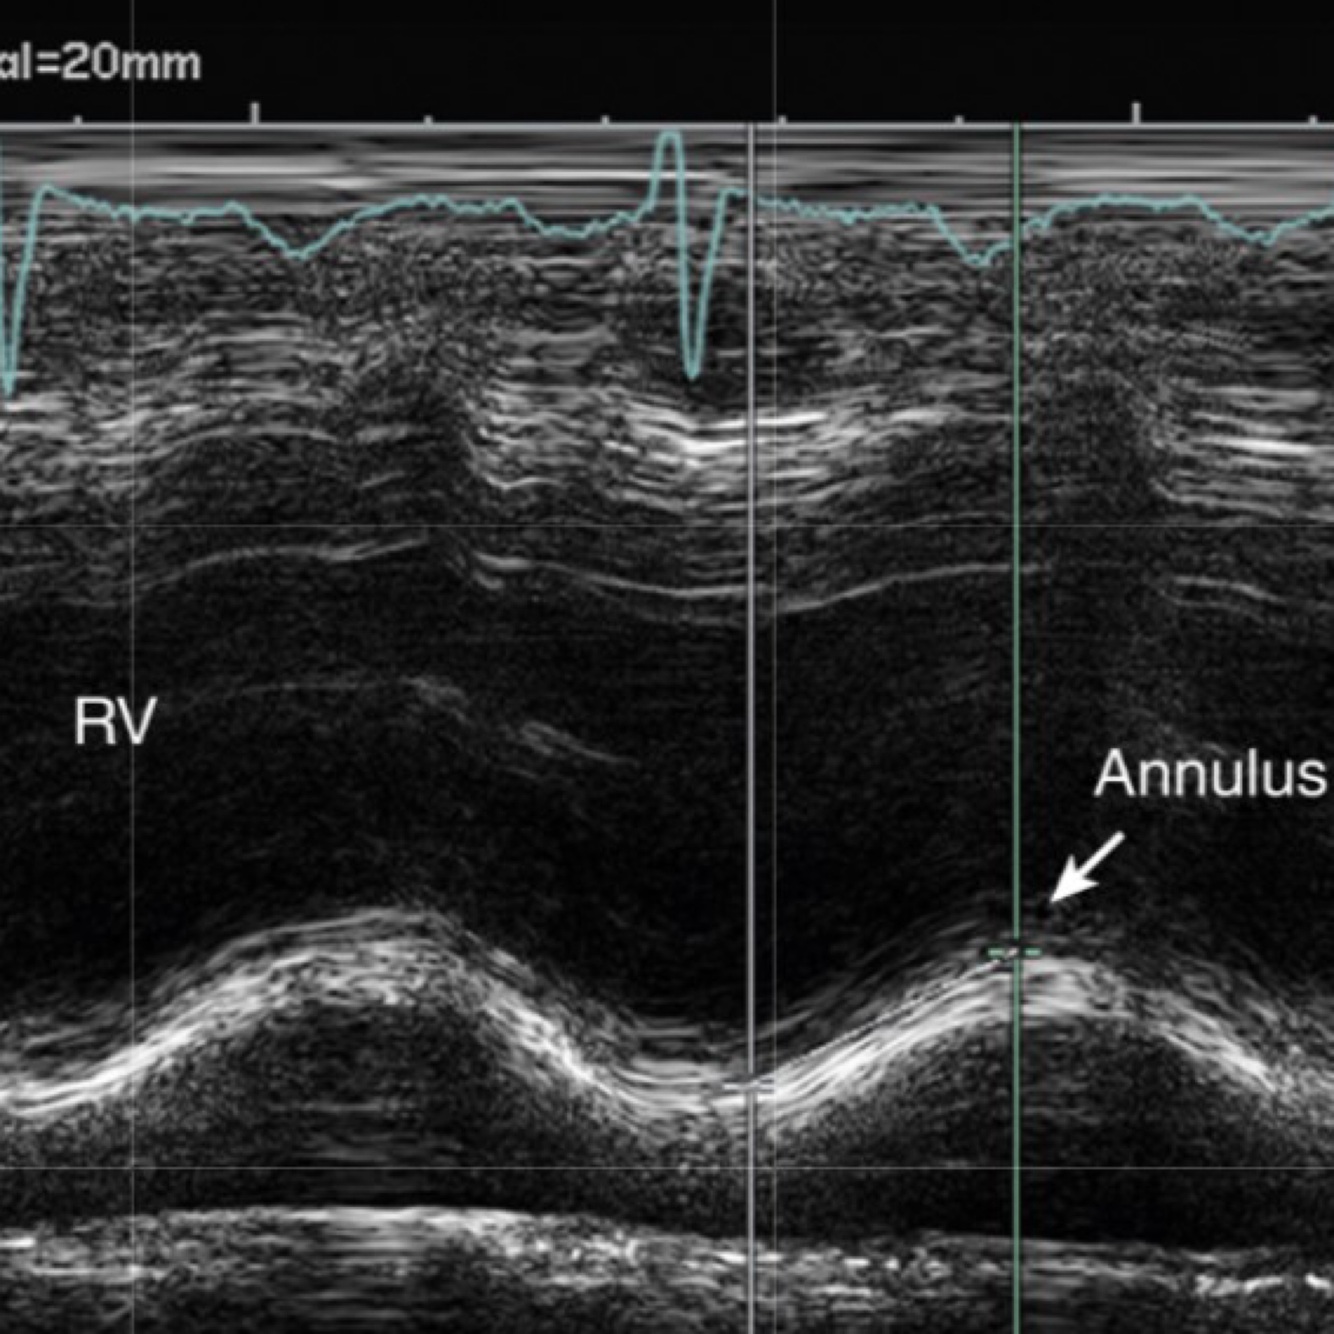

Q

This is a normal TAPSE? T/F?

A

True

Normal TAPSE >1.7cm